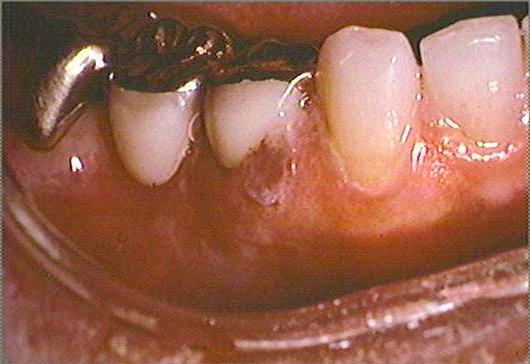

The skin on the right side of the face is erythematous and contains small vesicles and ulcers. Small ulcers are present on the right dorsum of the tongue, mucobuccal fold and the gingival papilla between the mandibular right central and lateral incisors. The mandibular right first and second molars and the surrounding mucosa are painful to palpation. The periapical radiograph reveals no evidence of periapical disease. The mandibular right first and second molars are responsive to pulp testing and give no evidence of pulpitis. No palpable lymph nodes are present.

mandibular anterior teeth and gingiva right mandibular teeth and mucobuccal fold